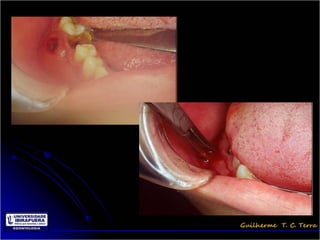

Pericoronarite

• Infecção dos tecidos moles (Opérculo)

que recobrem a coroa de um dente

incluso

• A dificuldade de higienização sob o

opérculo

Tratamento da Pericoronarite

• Limpeza mecânica do opérculo através de

irrigação com soro ou água oxigenada 10 vol

• Higienização dolocal pelo paciente e irrigações

com água oxigenada 10 vol

• Antibioticoterapia

• Exodontia